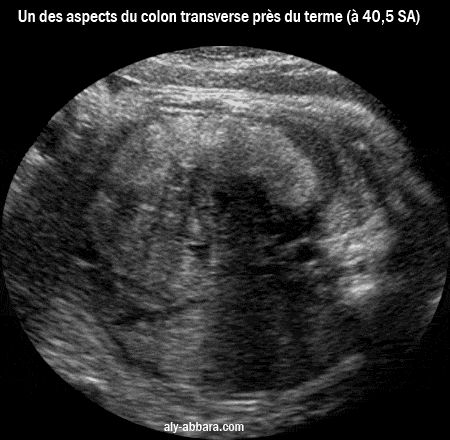

Image échographique montrant un des aspects physiologiques du côlon transverse chez un foetus âgé de de 39 SA et 4 jours, il s'agit d'un aspect normal du à l'occupation physiologique de la lumière du côlon par du méconium dense au cours des dernière semaines de la grossesse. (à comparer au méconium moins dense) |